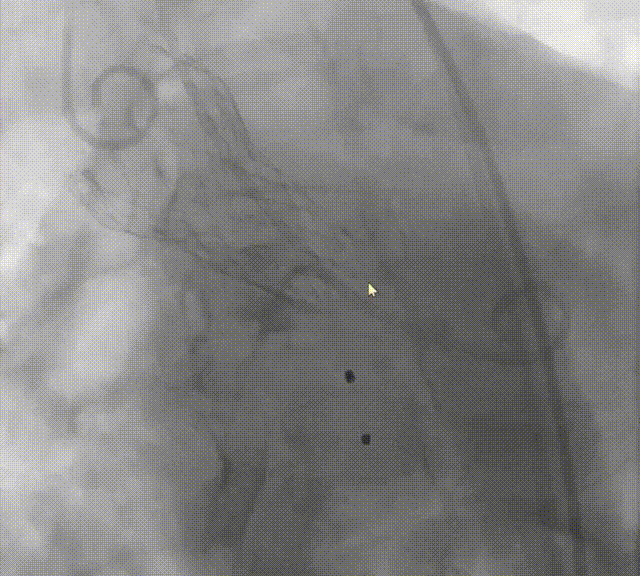

造影评估

跨瓣压差

术前120mmHg

释放后4mmHg

超声评估

后扩否?

瓣膜是否有弹出风险?如何避免?

再次与根部造影对比

通过与术前主动脉根部造影的对比,确认两侧深度平均但较临界,可谨慎操作下尝试球囊后扩张以使流入端瓣架充分膨胀贴合自体瓣环,减少瓣周漏。